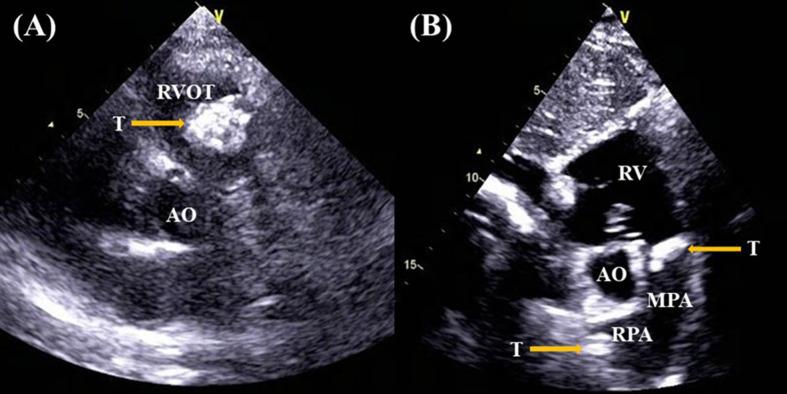

Primary cardiac myxofibrosarcoma is a rare form of cardiac malignant tumors. MFS usually involves the left atrium and presents as a unicentric or multicentric tumor mass. We reported on a 37-year-old female who presented with chest tightness and dyspnea for a month, dry cough, and occasionally having blood streak sputum for half a month. Echocardiography, cardiac computed tomography and cardiac positron emission tomography revealed multiple tumors in the heart. The right ventricle and right pulmonary artery were involved, with occlusion of the right pulmonary artery. Cardiac tumors were surgically resected and were consistent with low-grade MFS. No recurrence or metastasis occurred at 20 months of follow-up.

原发性心脏黏液纤维肉瘤是一种罕见的心脏恶性肿瘤形式。黏液纤维肉瘤通常累及左心房,表现为单中心或多中心肿瘤团块。我们报道了一名37岁女性,她出现胸闷、气短1个月,干咳,偶尔有血丝痰半个月。超声心动图、心脏计算机断层扫描和心脏正电子发射断层扫描显示心脏有多个肿瘤。右心室和右肺动脉受累,右肺动脉闭塞。心脏肿瘤经手术切除,符合低级别黏液纤维肉瘤。随访20个月未发生复发或转移。